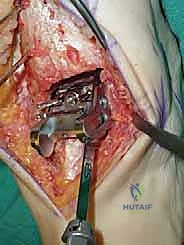

تتكون غرسة STAR من ثلاثة أجزاء رئيسية ولا تستخدم الأسمنت العظمي (Cementless)، بل تعتمد على النمو العظمي الدقيق داخل مسام الغرسة لتثبيتها بشكل دائم:

- المكون الظنبوبي (Tibial Component): صفيحة معدنية مسطحة من سبائك الكوبالت والكروم (Cobalt-Chromium)، تُثبت في أسفل عظمة الساق (الظنبوب) بواسطة أسطوانتين معدنيتين تدخلان في العظم لضمان الثبات المطلق.

- المكون الكاحلي (Talar Component): قطعة معدنية تغطي قبة عظم الكاحل، مصممة بشكل تشريحي منحني يحاكي تماماً شكل العظمة الأصلية، وتحتوي على أخدود طولي.

- الحشوة البلاستيكية المتحركة (Mobile Polyethylene Bearing): هذا هو سر نجاح غرسة STAR. هي قطعة من البلاستيك الطبي عالي الكثافة (UHMWPE) توضع بين القطعتين المعدنيتين. هذه القطعة ليست ثابتة، بل تنزلق بحرية للأمام والخلف، وتسمح بدرجة طفيفة من الدوران. هذا التصميم "المتحرك" يقلل بشكل هائل من إجهاد القص (Shear Stress) على واجهة العظم والمعدن، مما يقلل من احتمالية تخلخل الغرسة (Loosening) على المدى الطويل، ويمنح المريض نطاق حركة فسيولوجي مذهل.

تُعد هذه الجراحة من أروع وأدق الإجراءات في عالم جراحة العظام. يقوم الأستاذ الدكتور محمد هطيف وفريقه الطبي في صنعاء بتنفيذها وفق بروتوكول عالمي صارم لضمان نسب نجاح تقارب 100٪. فيما يلي تفصيل دقيق لخطوات العملية، مدعوماً بالصور من داخل غرفة العمليات.